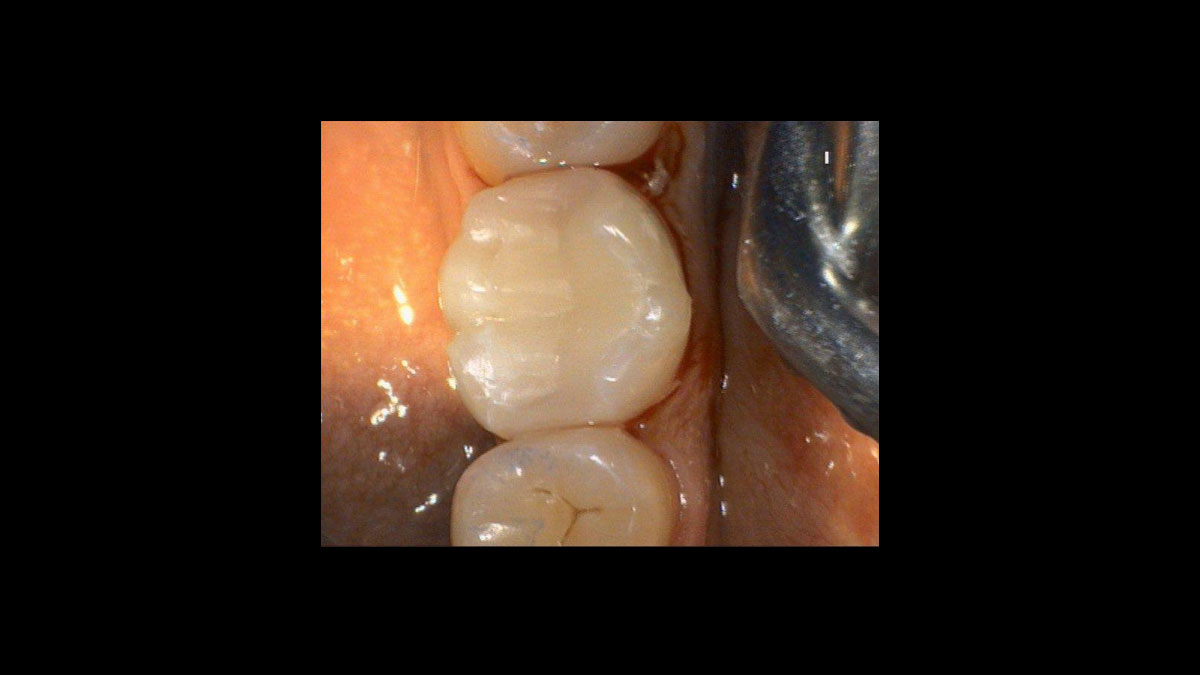

Gingivoplastie